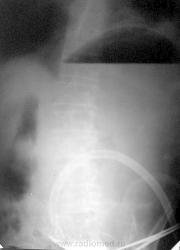

Пациенту на 5 день после тяжелого химического ожога пищевода наложили гастростому, и начали "кормить" шприцом Жане. Так продолжалось с неделю. Далее больной при появлении сестры с шприцом стал от неё убегать, прятаться и отказываться от кормления. Решили вызвать психиатра, но пока он не дошел - кто-то из хирургов вспомнил о рентгенологии. Для убедительности уговорили пациента еше на 50 грамм бариевой взвеси по гастростоме. Снимок перед Вами. Было это около 20 лет назад... Пришлось делать повторную операцию...

Значится есть стенозирование привратника. На операции рубец или опухоль?

Это был химический ожог с двойной локализацией непроходимости - в пищеводе и в выходном отделе желудка. Хирурги во время первой операции - по видимому не совсем адекватно оценили состояние пилоруса, и наступило быстрое его рубцовое сужение... А рентгенолог, к сожалению, второе сужение найти не мог - пищевод пострадал до полной непроходимости...

А может быть в пилорусе не успел так быстро  сформироваться стеноз, как в пищеводе?